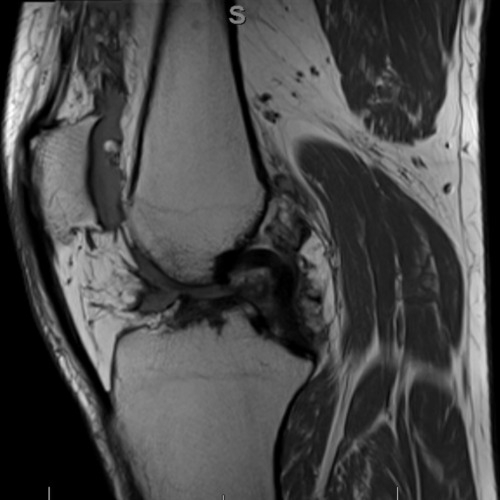

| An Unusual Cause Of Knee Swelling - Page #3 | |||